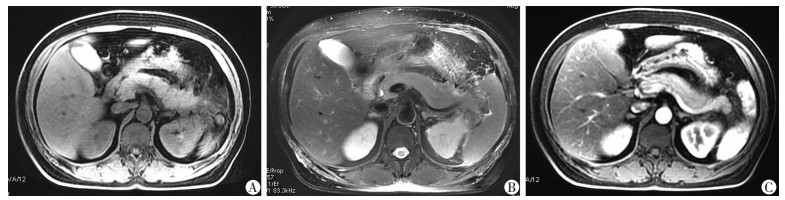

将IVIM-DWI与DTI原始图像数据传输至GE 4.4 Workstation。应用FuncTool 2软件包中的MADC软件和DTI软件对IVIM-DWI、DTI的原始数据进行后处理,以阈值法除去周围骨、气体、脂肪等组织的影像,获得MADC、DTI图,并测量其胰腺头、体、尾处感兴趣区(Region Of Interest,ROI)下单指数模型(Standard ADC)和双指数模型的参数值Slow ADC、Fast ADC、Ff ADC(图 1),以及DTI参数值ADC、FA,取胰腺头、体、尾的平均值为以上参数值(图 2)。ROI的选取:DWI图像上呈高信号区域(以T2WI图像作为依据)选取3个相同面积ROI测量各参数值,并连续测量上下三层面计算其平均值,尽量避开主副胰管、血管和明暗伪影带等。

| A:DTI图;B:ADC图;C:FA图选取胰体层面避开胰管用三个大小相等ROI测量各参数值 图 2 AP患者的DTI各参数测量图 |

2 结果 2.1 AP严重程度MRI评价85例AP中,糖尿病、高血压或高脂血症引起的28例,胆源性21例,饮食、饮酒19例,胆囊切除术后11例,其他6例。依据MRI表现,85例AP中间质水肿型66例(77.6 %),出血坏死型19例(22.4%),见图 3、4。依据MRSI分型:轻度32例(37.6 %),中度40例(47.05 %),重度13例(15.3%)。

|

箭头示:胰腺头、体、尾大面积液性坏死,呈长T1长T2改变 A:T1WI;B:T2WI;C:增强示坏死区未见强化,MRSI评分4+6分,严重程度为重度 图 4 出血坏死型AP患者(63岁男性)MRI表现 |